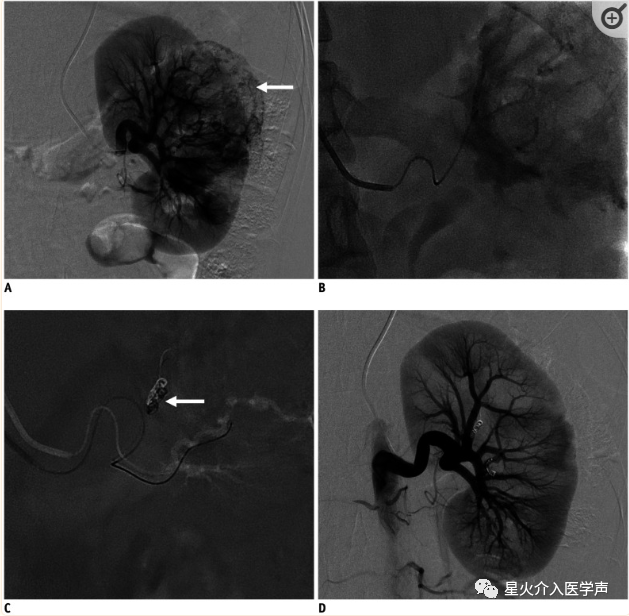

2.经桡肾动脉栓塞术

经皮动脉栓塞术(TAE)是治疗肾出血的一种安全有效的方法。例如,经皮影像引导肾动脉TAE是一种被广泛应用于肾创伤和肾血管平滑肌脂肪瘤患者的治疗方法(图8) (32).最近,TAE在肾细胞癌中的作用已被充分确定。肾细胞癌TAE可作为减少肿瘤血管供应和术中失血的技术,在非手术候选者中减轻肿瘤体积,缓解腹痛和血尿等症状。最近的研究表明,经皮肾动脉血管造影术和栓塞术可以采用桡动脉入路建立血管通路(18,34,35,36)。Abrams等人(36)报道了首例成功采用TRA进行肾动脉栓塞治疗妊娠患者出血性血管平滑肌脂肪瘤的病例,该患者不希望进行股动脉入路或盆腔放疗。在Srinivasa等人(18)的另一项研究中,发现TRA是一种安全可行的方法。

桡动脉鞘怎么读经桡动脉通路外周介入治疗最新综述_https://www.jmylbn.com_新闻资讯_第10张

图8:TRA在肾错构瘤栓塞术中的临床应用。

A.左肾动脉造影示右肾上极富血供肿瘤(箭头)。B.使用微导管选择肿瘤供血血管后,缓慢注入永久性栓塞剂(聚乙烯醇颗粒)直至血流停滞。C.微弹簧圈超选择性栓塞肿瘤供血血管(箭头)。D.栓塞后左肾动脉造影显示肿瘤血管完全阻断,肾实质灌注保留。